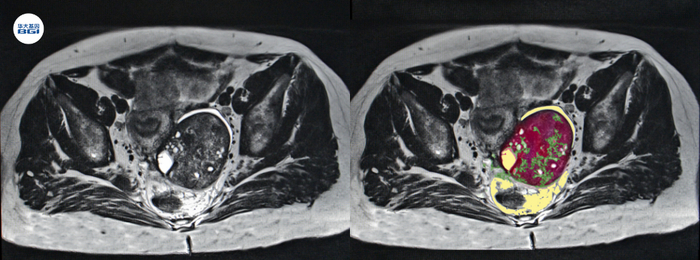

卵巢癌患者MRI图象